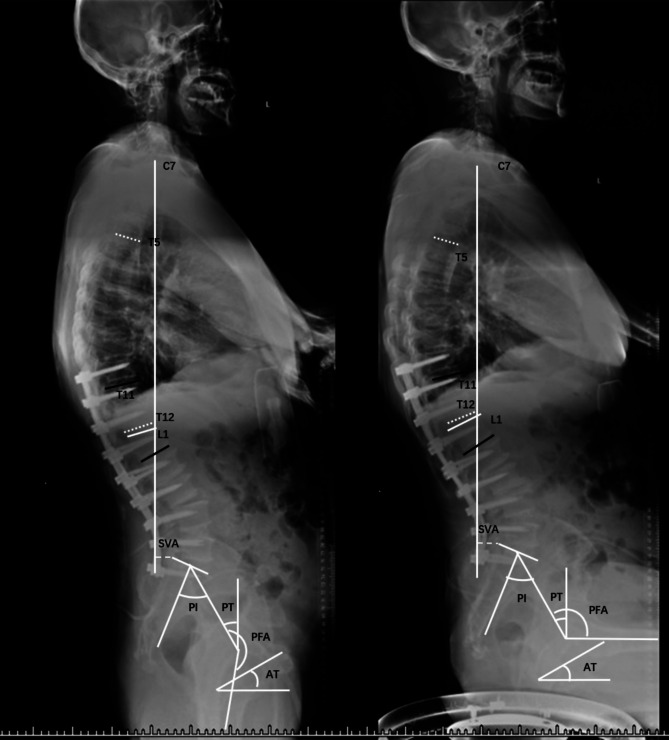

Methods: This cross-sectional study analyzed patients who underwent long- or short-segment instrumented fusion to the pelvis for lumbar degenerative disease at our hospital from June 2018 to October 2019. Patients were grouped based on the number of internal fixation segments, both short and long. Sagittal parameters were measured in standing and sitting positions and matched for sex, gender, height, weight, and other related parameters. Statistical analysis was performed using t-tests and Mann-Whitney U tests.

Results: A total of 98 patients were included, of whom 55 were included in the long-segmengroup (31 men, 24 women; mean age of 63.1 ± 8.5 years). In the long-segment group, no significant changes were observed between standing and sitting positions (P > 0.05). In the short-segment group, significant changes were observed in the sacral vertical axis, pelvic tilt, sacral slope, thoracic kyphosis, lumbar lordosis, T1 pelvic angle, T1 spinopelvic inclination, acetabular tilt, and pelvic-femoral angle between the two positions (P < 0.05). The difference in pelvic femoral angle changes between the groups was also significant (P < 0.05).

Conclusions: In the short-segment group, transitioning from standing to sitting leads to greater sagittal changes, including decreased lumbar lordosis and forward trunk lean, with smaller hip joints than in the long-segment internal fixation group.